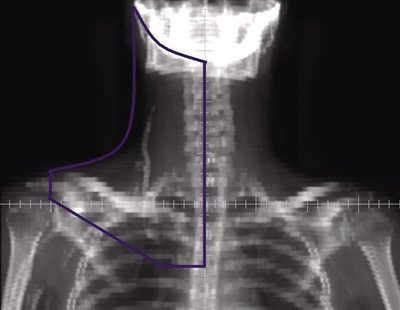

3 单颈纵隔野

肿瘤侵犯范围:纵隔淋巴结±肺门淋巴结和一侧颈部淋巴结。

靶区定义:纵隔、双侧肺门和一侧颈部区域,未包括耳前区(图3)。

上界:同侧上界为下颌骨体中线和乳突尖或耳垂连线,对侧上界位于颈6锥体上缘。

下界:隆突下5 cm或胸8椎体下缘或化疗前肿瘤下界下2 cm。

内界:颈部为体中线,保护未受侵一侧的上颈部。

外界:体中线左右各旁开4~5 cm,双锁骨上外界为肱骨头内缘。

肺门:包括1 cm边缘,若肺门受侵,包括1.5 cm边缘。